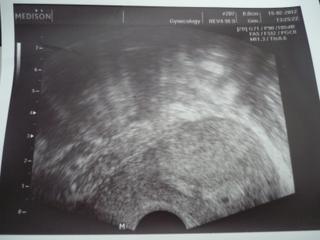

Moje tecka, pred tydnem byla placata, dnes kulata, ale pani doktorce se to nelibi, posledni ms byla 4.1, mela bych byt 5+5, ale ovulka byla az 21-23 DC, tzn. ze dnes jsem teprve +- 20 az 22 DPO...ale porovnavala to s utz minuly tyden a pry to nevyrostlo a tak to vidi spatne.odebrano hcg, zitra vysledky,.........moc se bojim........pekne jsem si porvala....i kdyz nadeje umira posledni.....

@jane84 dekuju....ona proste dneska mluvila hrozne definitivne, rovnou zacala o tom, ze nas necha vysetrit, ze ted uz na to mame pravo..proste to brala jako hotovou vec...az nakonec rekla ze jedine kdyby ovu byla pozdeji...ale pak zase ze proste tam neni ten vyvoj....ja nevim nejsem slozena, jen se hrozne bojim...ale mimiskovi verim....porad me poboliva bricho jako na ms ... snad mimisek vydrzi a snad to neni tak zle jak me dnes rekla :(